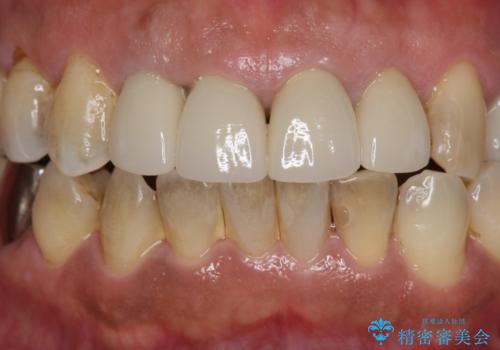

- 10数年前に治療した上顎前歯のクラウンをやり替え、審美性を回復したいと希望され来院されました。

X線写真より問題のなかった根管治療は行わず、クラウンを除去し仮歯でを装着したのちジルコニアクラウンを製作していきます。

茶しぶの目立つ下顎前歯はPMTCを行うことで歯の自然な白さを回復しました。

- 48.4万円(税込)(仮歯・ジルコニアクラウン×4)費用は治療当時の料金となります